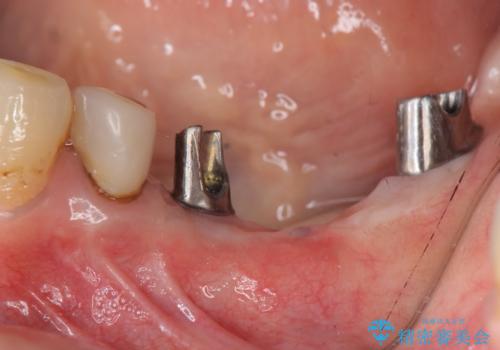

- 左下に長年使用した入れ歯が合わず、よりしっかりと噛みたいという希望で来院されました。

入れ歯をはずししっかりと噛む手段としてインプラント治療を進めていきます。

- 90万円(ストローマンインプラント×2・チタンカスタムアバットメント×2・ジルコニアクラウン×3)費用は治療当時の料金となります